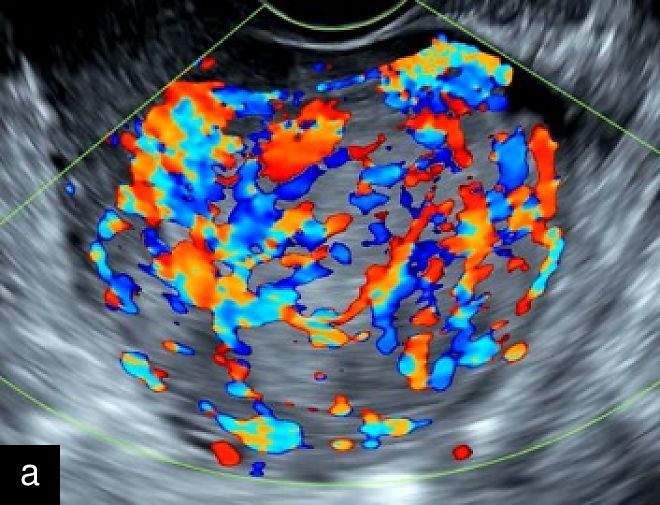

A retrospective series of 20 STUMPs further described most lesions as well-defined (85%), with non-uniform echogenicity, isoechoic (60%) or mixed echogenicity (30%) and microcystic anechoic areas (70%). No shadowing and no calcifications were reported. No calcifications or shadowing were observed, and the vascularization was predominantly poor-to-moderate (69%), with both circumferential and intralesional blood flow patterns being common (90%)28 (Figure 4).

4

Grayscale (a) and color Doppler (b) transvaginal ultrasound images of a STUMP showing a heterogeneous mass with irregular echotexture. (b) Doppler imaging highlights scattered vascularization, with a color score of 3, indicating moderate vascularity and a potentially atypical neovascularization pattern.